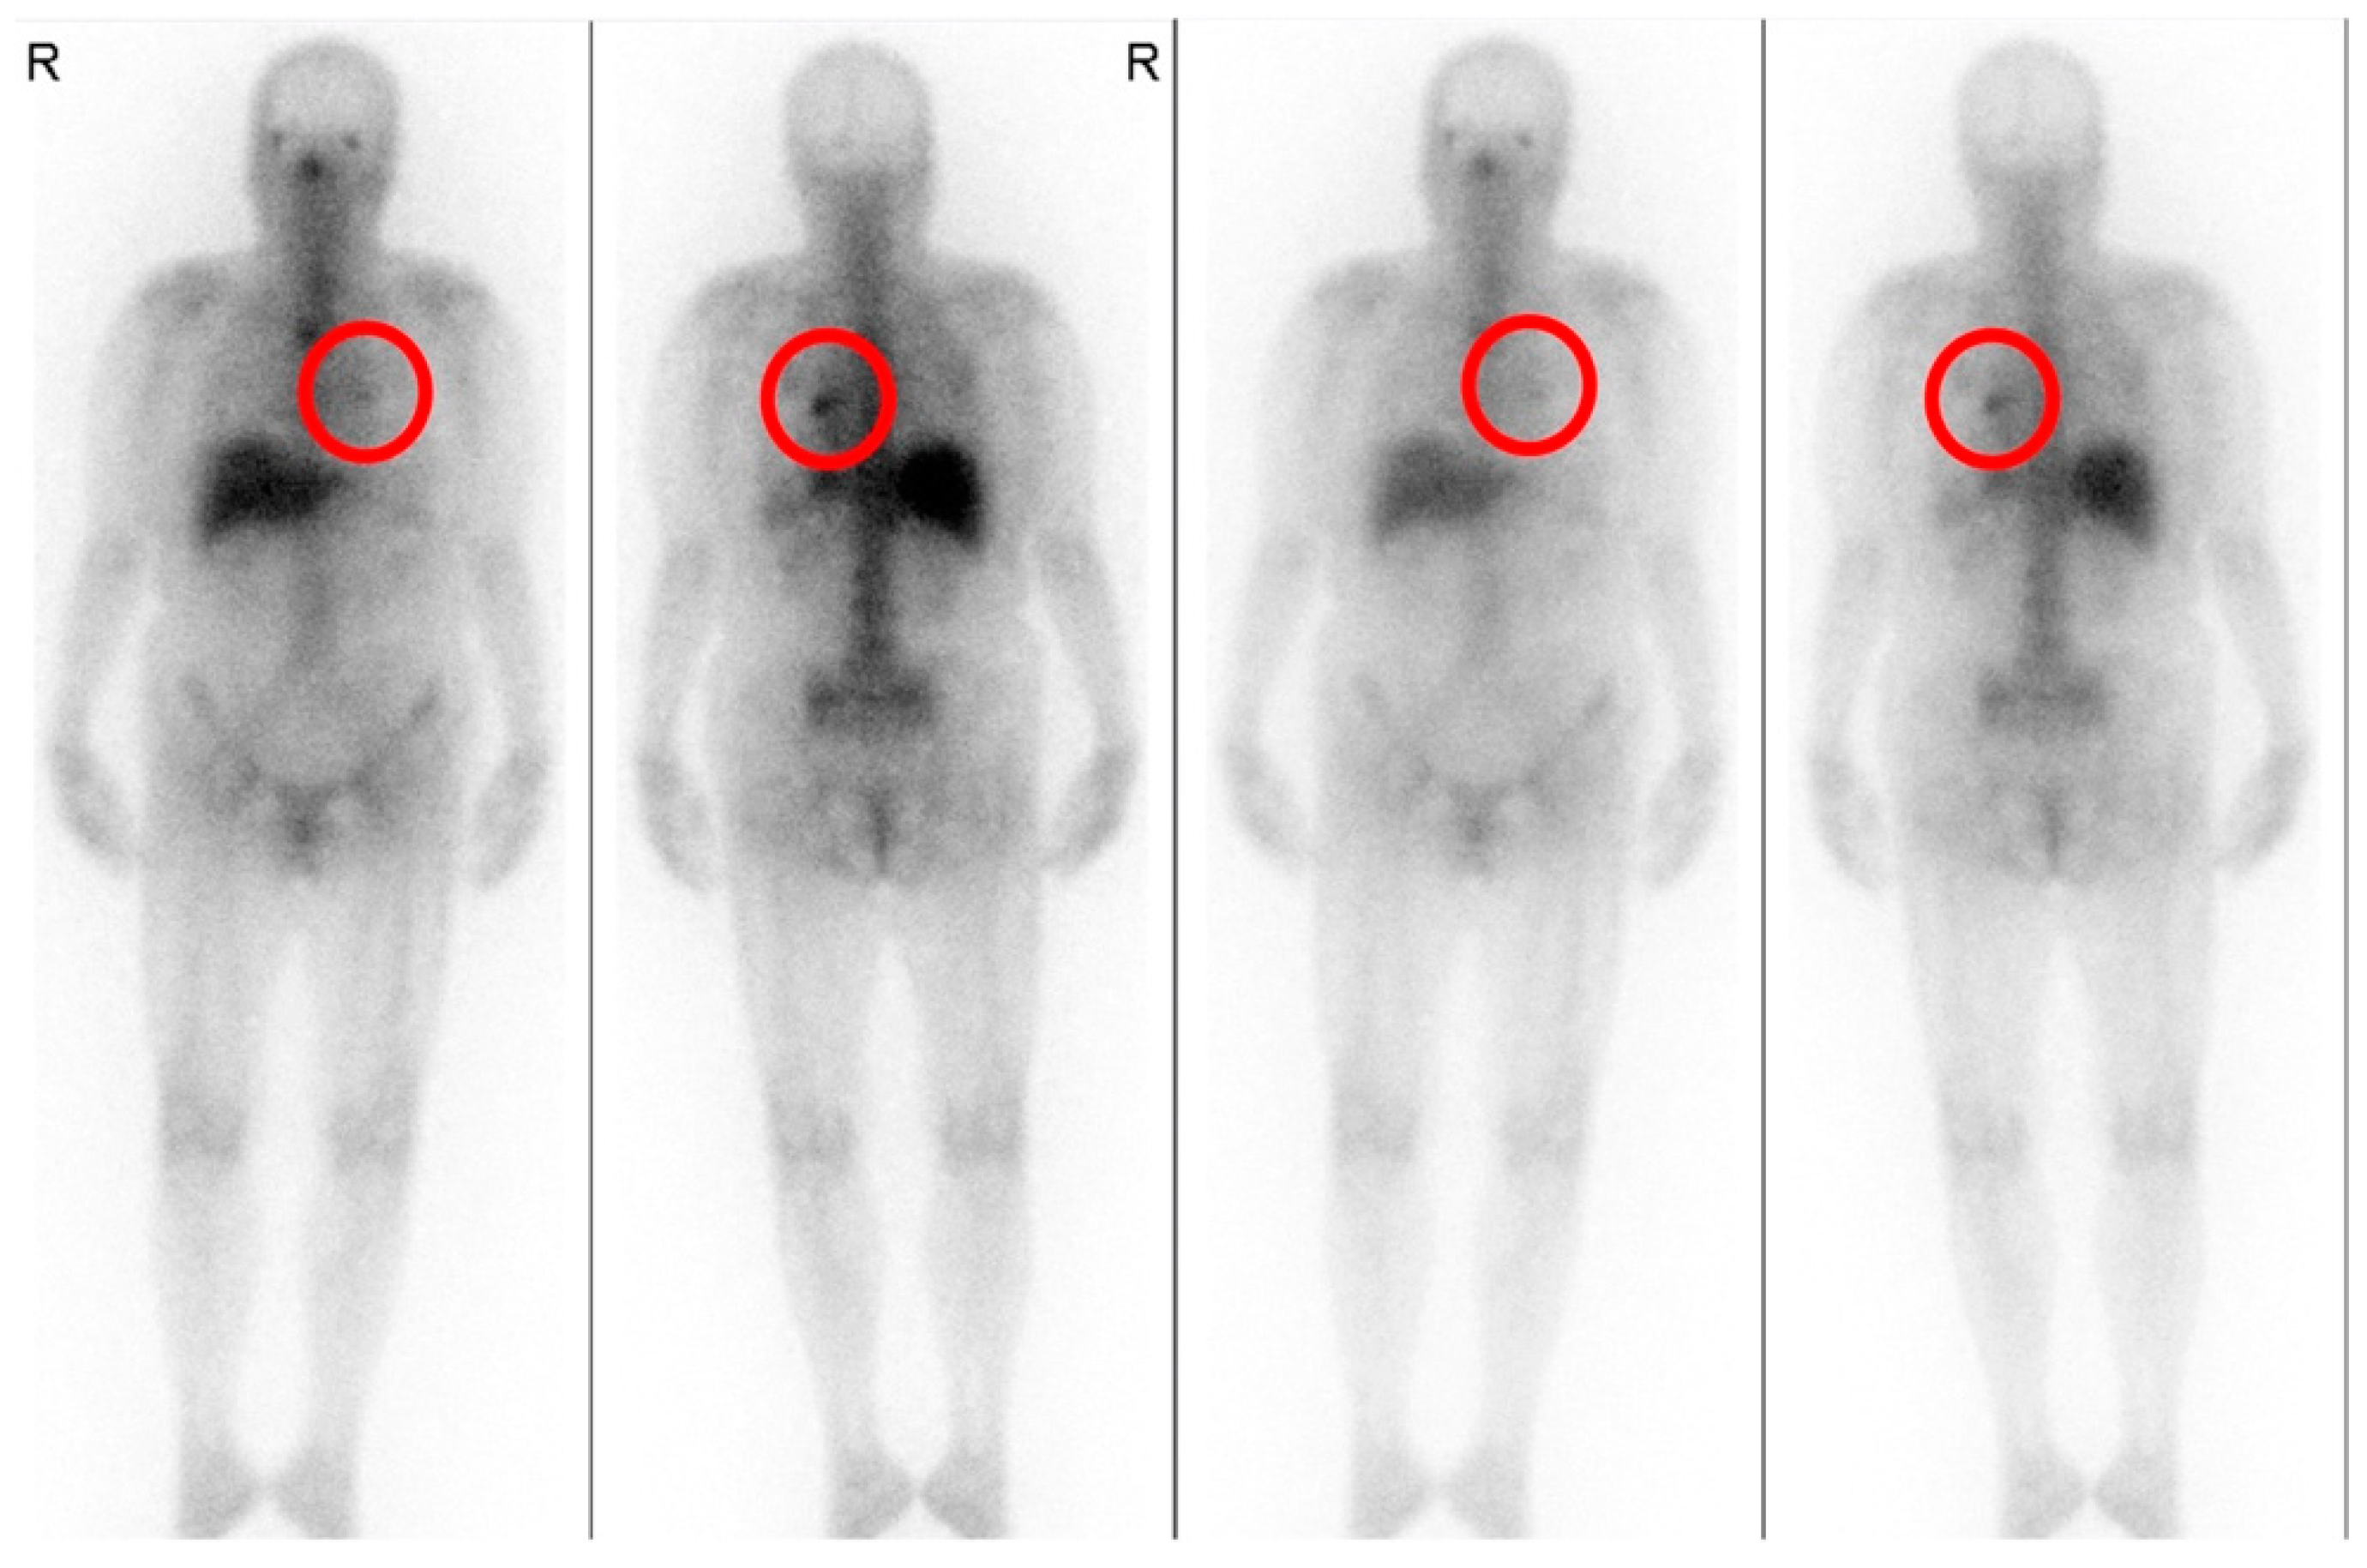

At 12 months postoperatively, a contrast-enhanced CT showed that the infiltrative shadows in the lung fields were reduced, and the endoleak had disappeared (Figure 4). No inflammation was observed, and blood in the sputum had disappeared, indicating a good postoperative course.

Figure 4. (ac) Contrast-enhanced computed tomography at 12 months postoperatively shows infiltrative shadows in the lung fields around the graft and improvement of gaseous images (arrows). (d) No abnormality in the stent graft or endoleaks was observed.